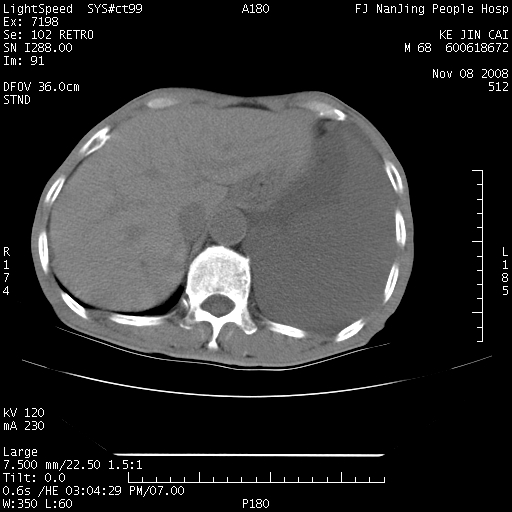

是个很有看头的病例,咋人气那么不旺?没多少人兴趣呢?这个病例几大怪:1   恶性肿瘤侵犯心肌左房怪,心肌一般不会被恶性肿瘤侵犯吧?2   左下肺均匀实变怪,内无含气,有别一般不张实变,含气肺泡完全为液体取代,而非一般不张实变的肺萎陷,冷不丁还以为是肿大的脾脏3   肿瘤本身怪,像tb肺不张4   这么有看头的病例没人气怪。呵呵。

追查病史,咳嗽,患者无发热,血象不高。据说2年前胸片检查怀疑肺ca曾行纤支镜检查,病理未见到癌细胞。无确切资料。

左肺恶性肿瘤侵犯肺动脉,左心房内瘤栓,胸膜转移。